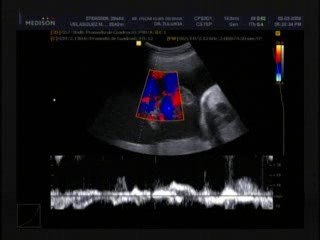

Ecografia Ostetrica 20 settimane